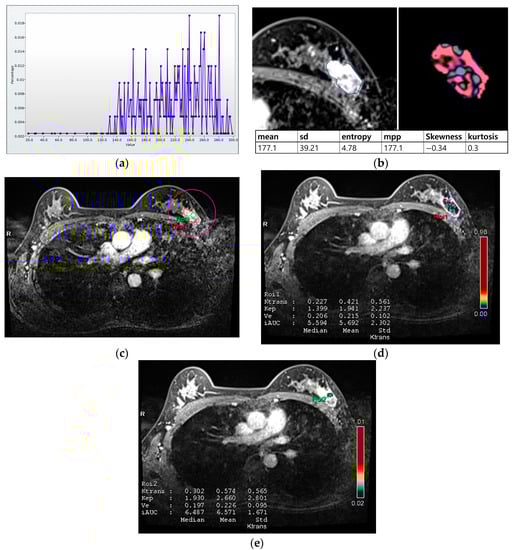

For histogram analysis, a region of interest (ROI) was drawn along the entire tumor enhancement on PostcontrastT1 in the largest cross-sectional area of the tumor, and this was then used for PrecontrastT1 and T2 lesions corresponding to those on PostcontrastT1. After tumor segmentation, six parameters were extracted from each ROI without filtering: (a) mean pixel intensity, (b) standard deviation (variation from the mean), (c) means of positive pixels (the average gray level intensity above zero threshold), (d) entropy (the randomness of gray-level distribution), (e) kurtosis (the peakedness of the distribution), and (f) skewness (asymmetry of the distribution) (Figure 2a,b).

Figure 2.

Histogram and perfusion analyses conducted on breast MRI in a 42-year-old woman with a 30 mm triple-negative invasive ductal carcinoma of the left breast (a,b). Histogram analysis on MRI: Axial contrast-enhanced T1-weighted MRI image shows an oval shaped, irregular marginated, and heterogeneous enhancing mass in the left breast. The region of interest (ROI) was drawn manually for the entire tumor, and a histogram was obtained (a). From the histogram, six statistically based metrics were extracted: mean, standard deviation (SD), mean of positive pixels (MPP), entropy, skewness, and kurtosis (b). (c–e) Perfusion analysis on MRI: Two ROIs (ROI1: entire tumor and ROI2: hot spot) were manually delineated (c), and eight perfusion parameters from each ROI were obtained: median and mean values of Ktrans, kep, Ve, and iAUC (d,e).

For perfusion analysis, measurements were made in two ROIs for the entire tumor and hot spot (high perfusion area within the tumor; Figure 2c–e). Perfusion parameters were calculated using voxel-wise T1 perfusion maps, gadolinium concentration–time, arterial course input function, and fitting with a pharmacokinetic model. Four perfusion parameters were extracted from two ROIs for each tumor: (a) Ktrans (the constant representing the transfer of contrast medium from blood plasma to the extracellular extravascular space per minute), (b) kep (the rate constant representing transfer of contrast medium from the extracellular extravascular space into blood plasma per minute), (c) Ve (the extracellular extravascular space per unit volume of tissue), and (d) iAUC (the initial area under the contrast concentration–time) [,,]. The hot spot was selected as the high perfusion area on the Ktrans-based perfusion map. The median and mean values of each parameter were automatically calculated from the two ROIs.